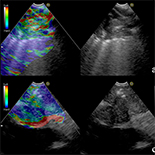

Ultrasound elastography is an imaging modality used to show tissue stiffness in tumor pathophysiological processes that promote the formation of stiffer tissues. Endobronchial ultrasound (EBUS) elastography is an ultrasound elastography-based technique for measuring tissue stiffness during EBUS-guided transbronchial needle aspiration (EBUS-TBNA). The diagnostic value of EBUS elastography in central lung lesions remains largely unknown.

A total of 57 patients with central lung lesions underwent ultrasonic bronchoscope examination. EBUS with standard B mode evaluation and elastography with grading score measurement were performed before EBUS-guided transbronchial needle aspiration (EBUS-TBNA). Comparison of the diagnosis accuracy in malignant lung lesions between elastography and standard EBUS was made.

Our data showed that the hypoechoic lesions, uneven echo, distinct boundary, and no air bronchogram were significant indicators of standard EBUS in diagnosis of malignant lung lesions (P<0.01). The differences in elastosonography grading scores between the benign and malignant lung lesions were statistically significance (P<0.01), and the elastography grading score was more sensitive and specific than the standard EBUS criteria in diagnosing malignant lung lesions. The area under the receiver operating characteristic curve (ROC) for the elastography grading score was 0.793. The best cut-off point of the elastography grading score for distinguishing malignant from benign lung lesions was 2.5. The elastography grading score had a sensitivity of 72.2%, specificity of 76.2%, positive predictive value of 83.4%, and negative predictive value of 61.5% for distinguishing malignant from benign lung lesions. The overall accuracy of elastography grading score was 73.7%.